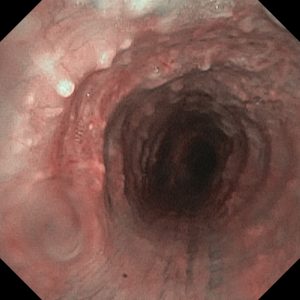

В эндоскопическом атласе обычно представлены изображения и видео, полученные во время процедур, проводимых врачами-эндоскопистами. Эти изображения и видео могут использоваться для обучения студентов медицинских учебных заведений, повышения квалификации медицинских работников, а также для консультации врачей при диагностике и лечении различных заболеваний.